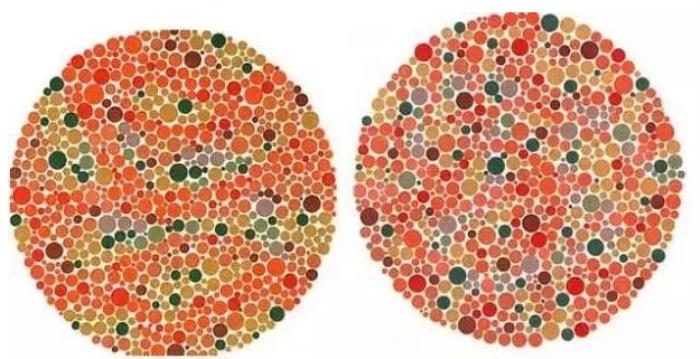

终极测试!!下面这张图你看到了什么数字?

结果:

左图:全色弱者及正常者读不出来,红绿色盲者及红绿色弱者大多能看到5

右图:正常者及全色弱者大多找不到,红绿色盲者及红绿色弱者容易找到

欢迎大家来评论一起猜一猜!